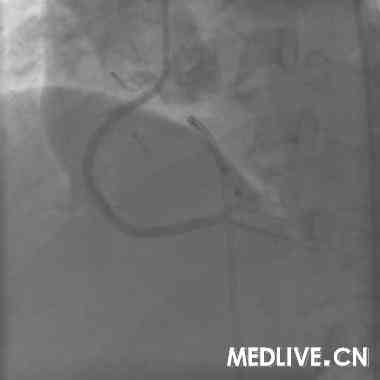

术前血管造影(附图):

冠造结果(图2-4):回旋支中段100%闭塞;右冠中段100%,并见大量血栓影;前降支中段不规则狭窄50%。结合临床,考虑右冠为急性心肌梗死相关冠脉,应首先对其进行急诊介入治疗。

手术过程(附图):

经右股动脉途径,6F,JR4.0引导管,HT BMW Universal引导丝顺利通过右冠闭塞病变部位,Diver血栓抽吸导管于病变部位及其近、远段部位连续抽吸,反复5次,造影可见右冠血流恢复,余狭窄最重部位直接植入Excel支架3.5*14mm,12atm释放,16atm原位后扩张,最重效果满意,右冠TIMI血流3级(图5-7)。